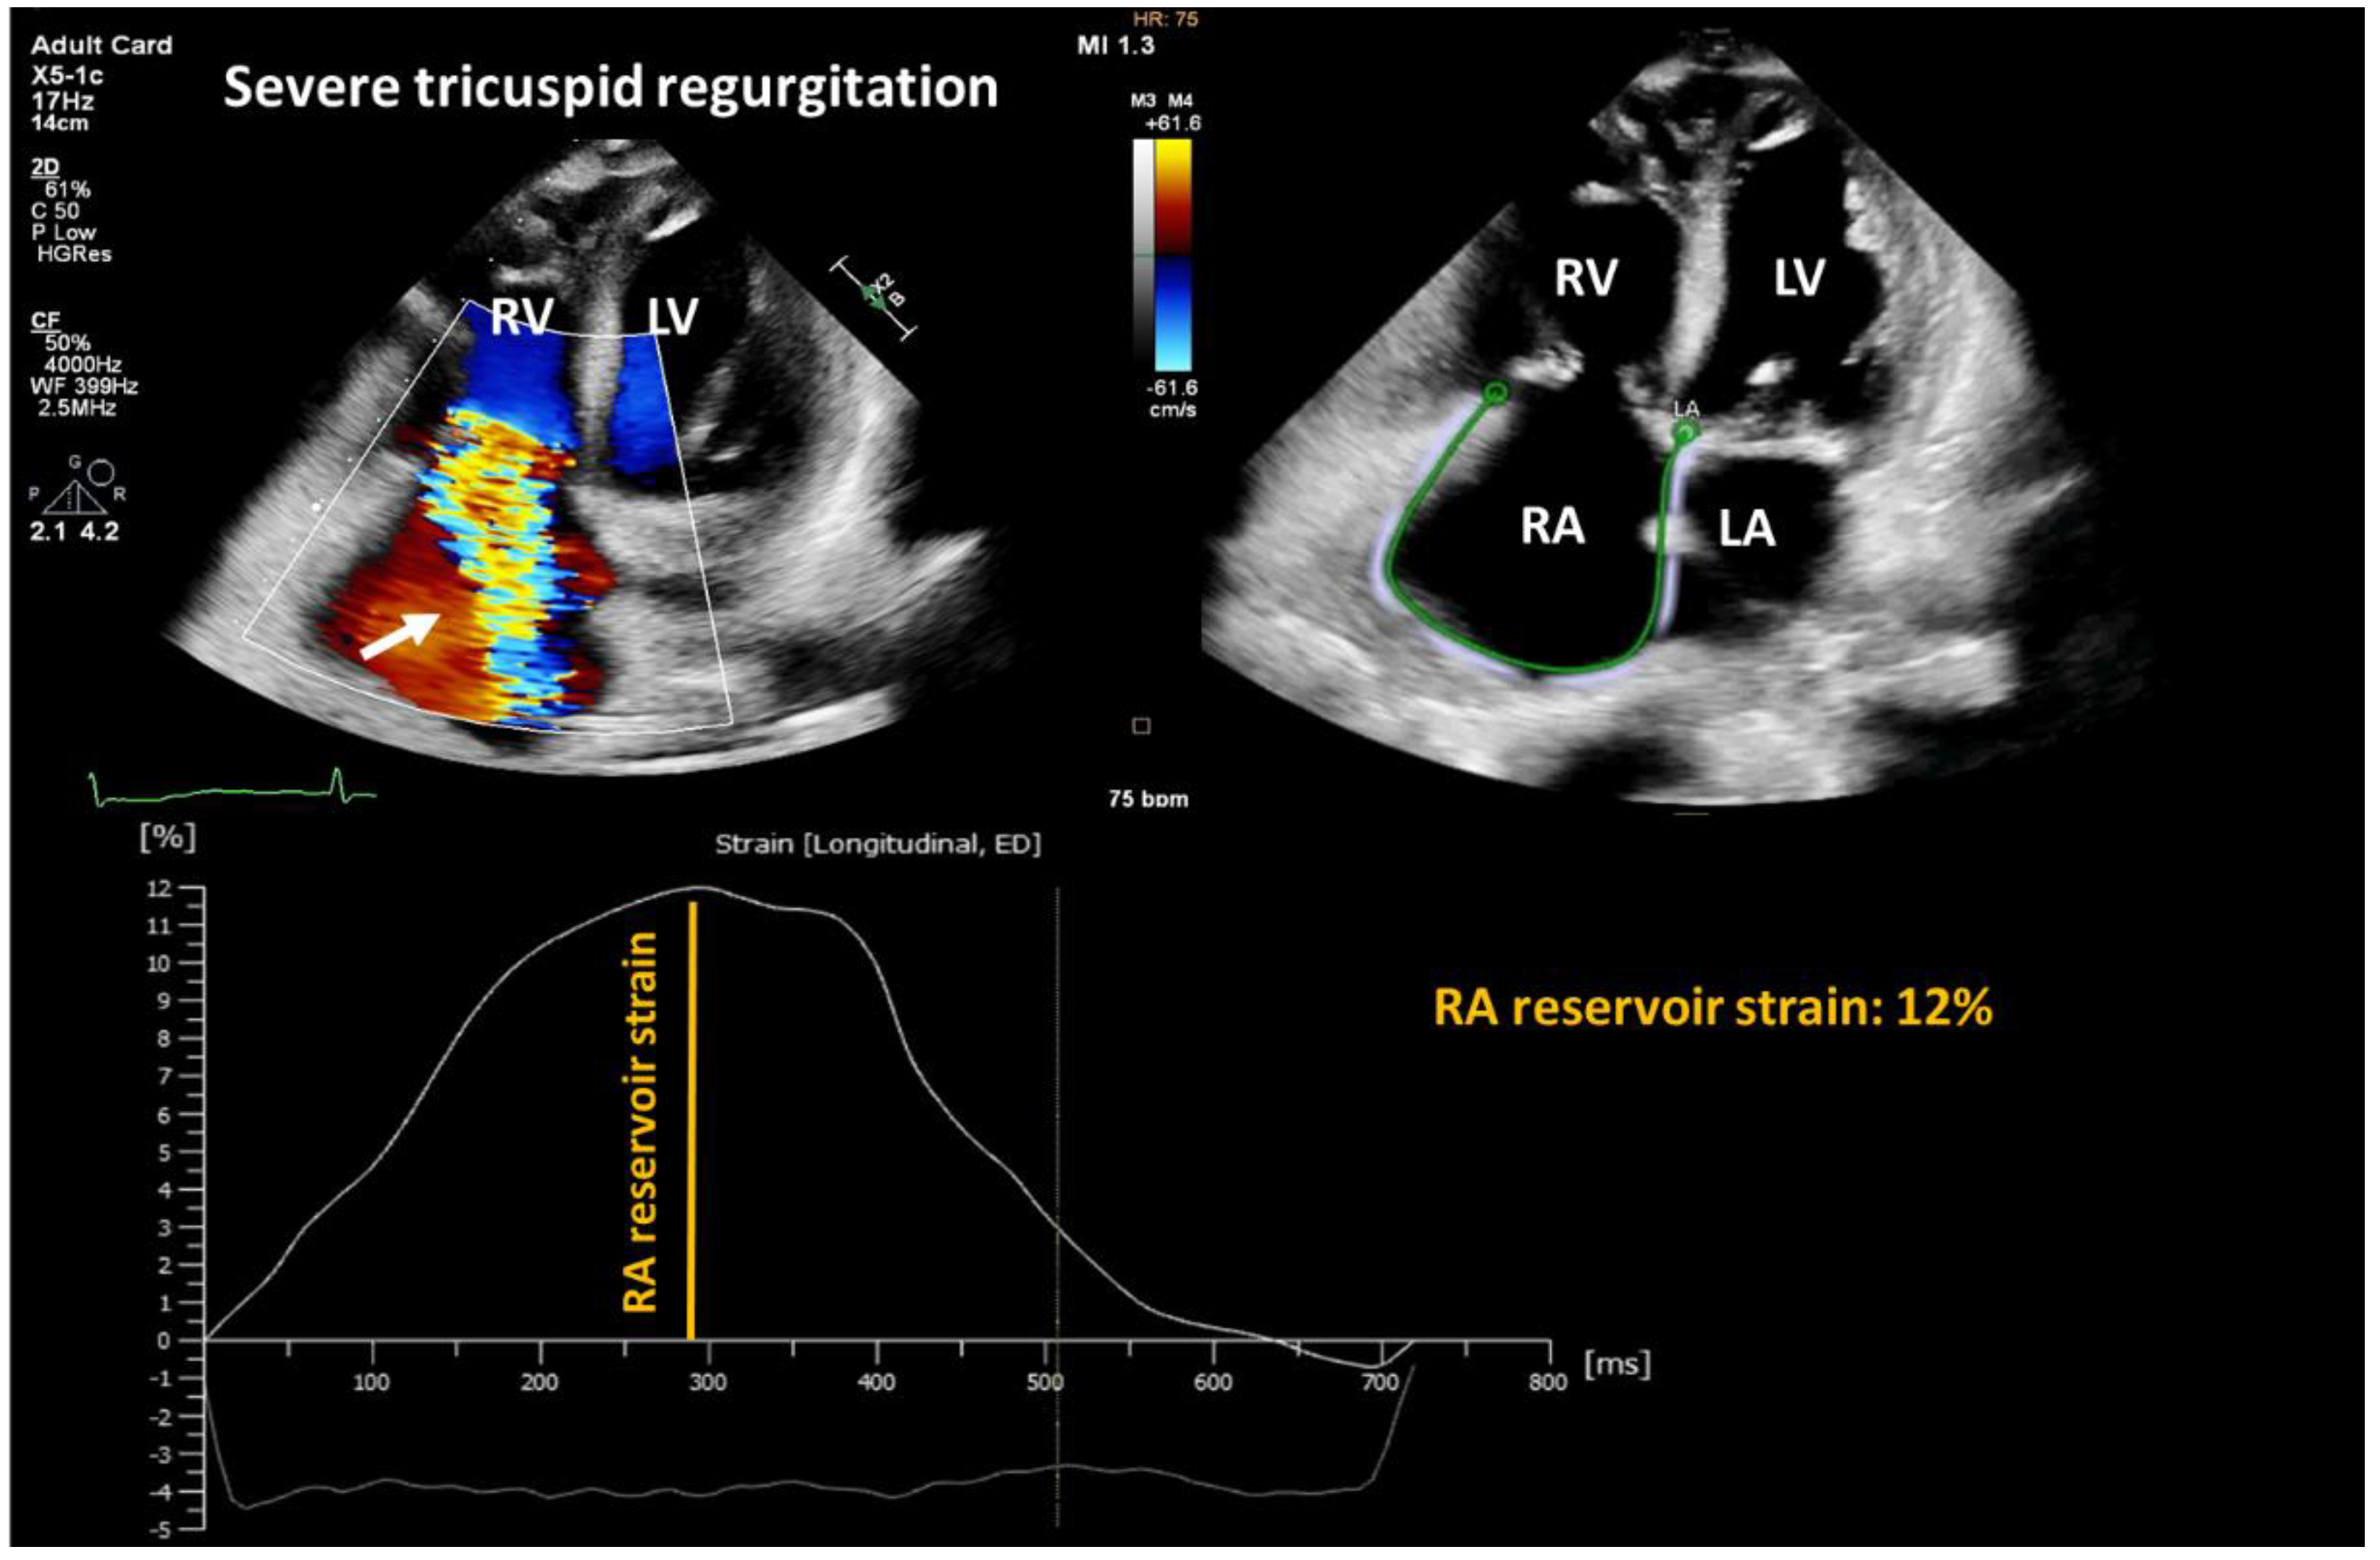

Figure 5.

Representative two-dimensional transthoracic echocardiography image showing severe tricuspid regurgitation (white arrow) and decreased right atrial reservoir function. RA: right atrium; LA: left atrium; RV: right ventricle; LV: left ventricle.